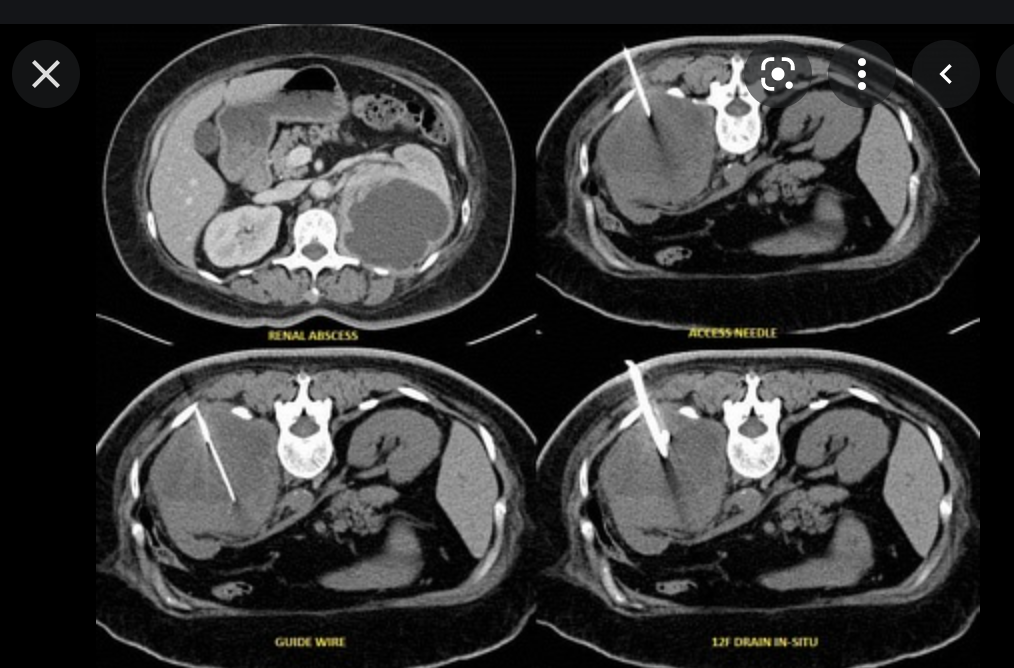

What are the two techniques used to percutaneous treat abdominal/pelvic collections

- Trocar technique

- commonly performed for large abscessers or collections with easy access.

- localise abscess by CT or US

- Anesthetize skin

- make skin nick and perforate subcut tissues

- place 8-16Fr abscess drainage catheter in tandem. Remove stylet

- Aspirate all fluid

- send for culture

- wash cavity with saline

- commonly performed for large abscessers or collections with easy access.

- Seldinger technique

- this is commonly performed for abscesses with difficult access or for necrotic tumours with hard rims

- localize abscess

- anesthetize skin

- localize abscess with 4, 6, or 8 inch seldinger or chiba needle (18gauge or 19gauge thin wall) under imaging guidance

- remove needle, leave outer sheath

- pass guide wire through sheath into abscess cavity

- dilate tract (8, 10, 12 Fn) over stiff guide wire

- Remove stiffener and guide wire.

- aspirate abscess

- this is commonly performed for abscesses with difficult access or for necrotic tumours with hard rims